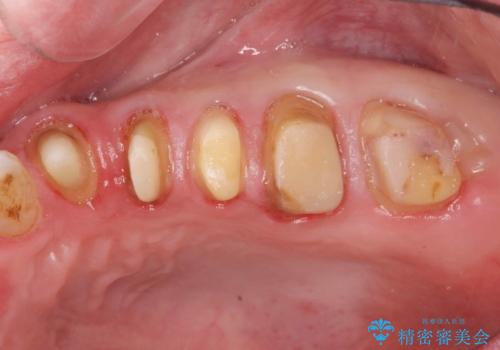

- 銀歯・虫歯・治療途中の歯を治していきたい、セラミックの歯にしたい!と希望され来院されました。

銀歯の下で再発した虫歯や、根尖病変等、多々の問題が認められましたがひとつづつ丁寧に改善し、長期的な予後の見込めるセラミック治療を行っていきます。